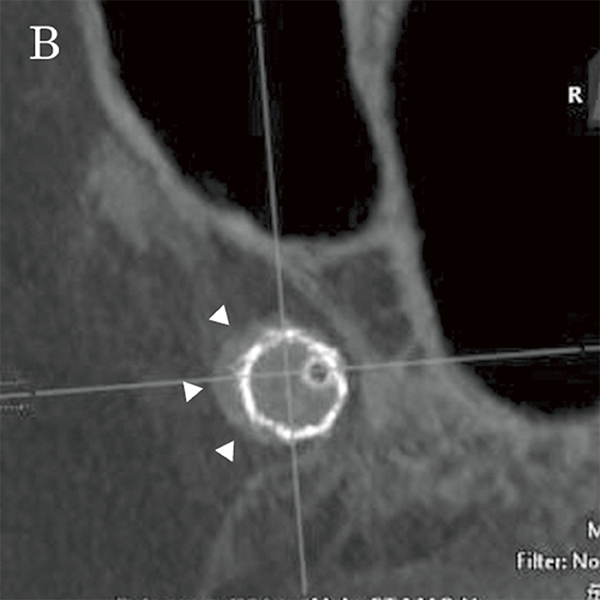

На основі цих вимірювань було обрано пристрій для емболізації Pipeline™ (PED) (4,75 мм × 16 мм; Medtronic, Японія), аневризму лікували, спостерігаючи за флюорографічними зображеннями детектора високої чіткості (мал. 5A та 5B). Пристрій було розгорнуто від C2 (біфуркація задньої сполучної артерії) до C4, а розгортання FD і стан кримпування материнської судини підтверджено Alpha CT (мал. 6A і 6B).

Малюнок 6B: Візуалізація Alpha CT після розміщення FD.

Малюнок 7B: Мультипланарна реконструкція Alpha CT після розміщення FD. Стрілками показано ознаки поганого розгортання (коротка вісь на проксимальному кінці).